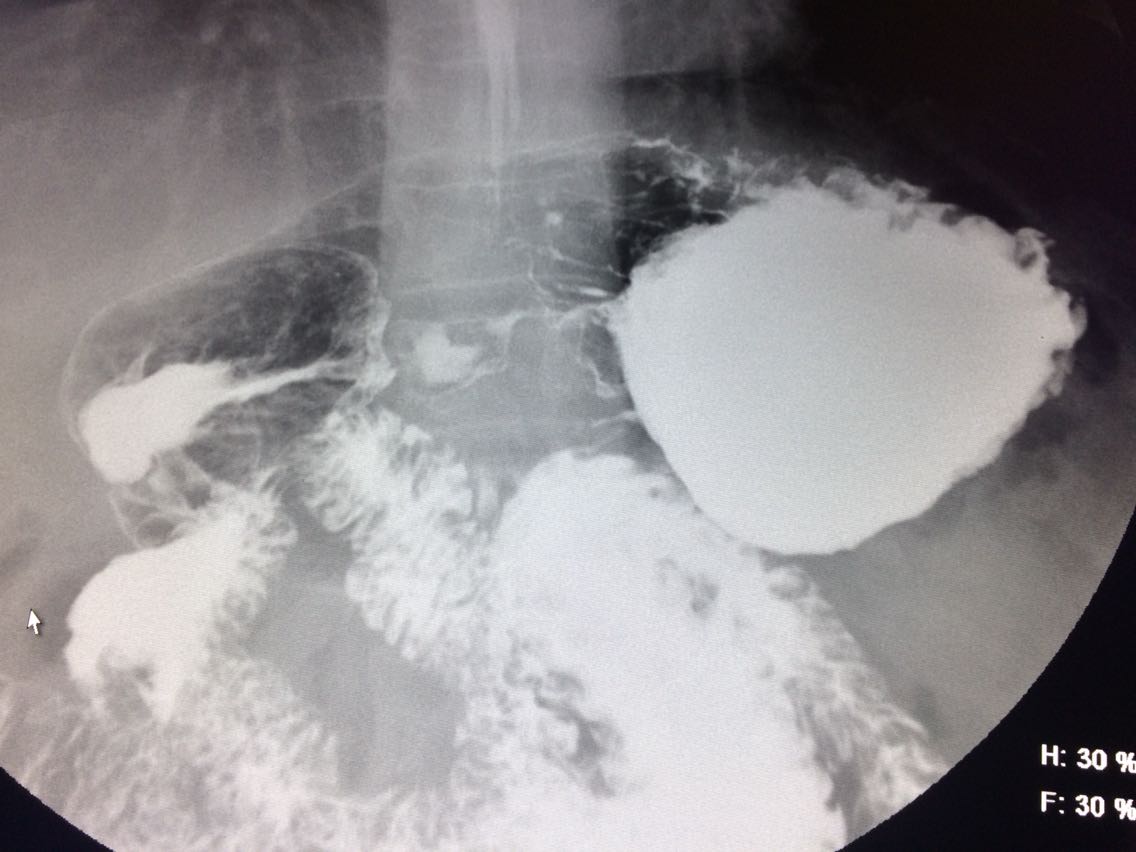

一例溃疡型胃癌。

男,45岁 反复胃疼5年余。 5年来,反复出现胃疼,进食后半小时加重,经常感觉饥饿,当地按胃溃疡,给予阿莫西林,奥美拉唑治疗,具体不详,效果欠佳,遂入院,入院来,饮食睡眠,二便可。 既往体健。 入院上消化道造影如图。

讨论,诊断及鉴别诊断? 胃溃疡的影像表现? 溃疡良恶性的鉴别? 入院后行胃大部切除术。 诊断,胃腺癌。